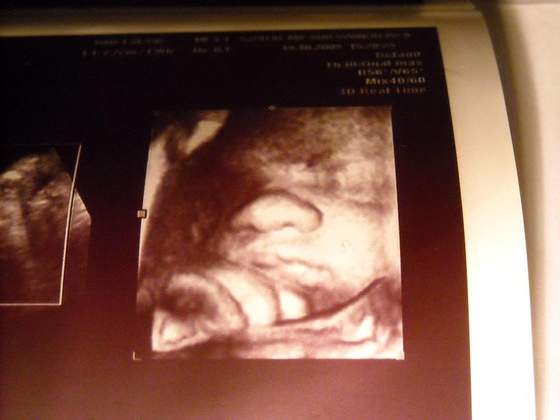

U nas wczoraj na usg (18 t) moi mali panowie przytyli dość sporo w ciągu dwóch tygodni. Teraz mają ok. 230g.:-)Ponoć są bezwstydni, pokazują siusiorki bez krępacji:-).

a my juz dziasiaj po usg maluszki rozwiajaja sie perfekt K-966G O- 1008g ehhh moje szkarabki kofanee